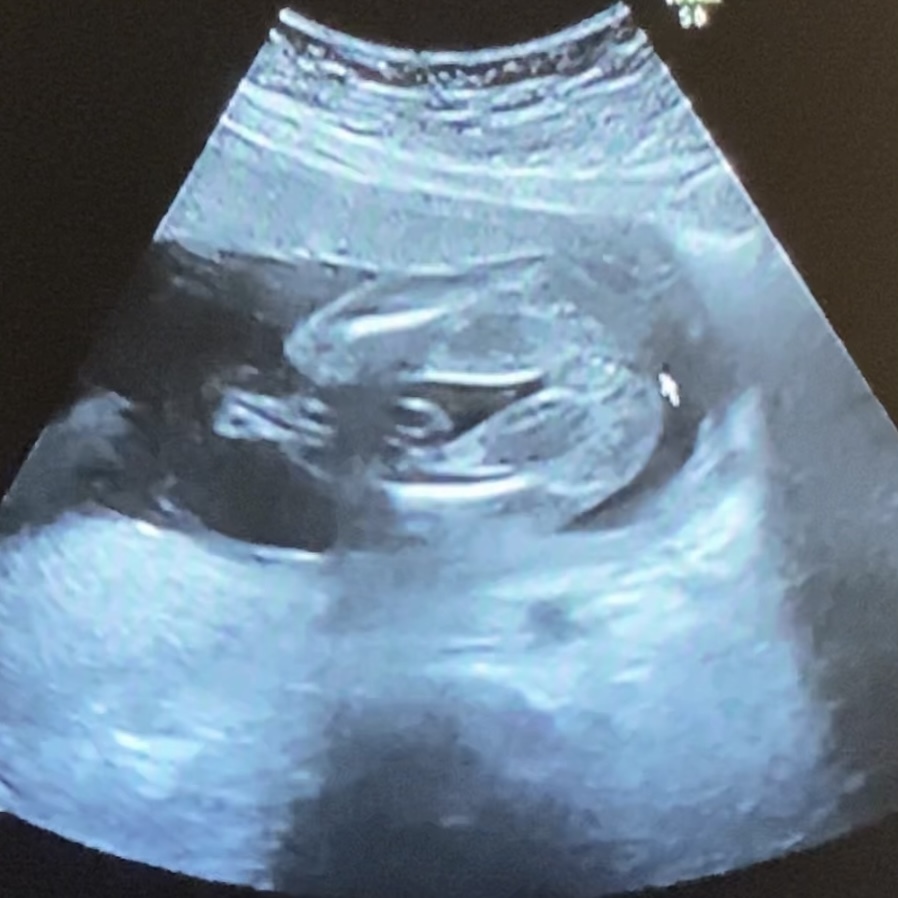

エコー写真は、おなかの赤ちゃんの様子や性別などを確認することができます。 妊娠4ヶ月や5ヶ月ぐらいで性別が分かるのはエコー写真のおかげです。またダウン症や口唇口蓋裂の可能性も確認することができます。 男の子のエコー写真の特徴 胎児の両足の間を見てください。男の子であればそしてエコー写真で性別 が しかし16週頃の赤ちゃんには、男の子でも女の子でも突起物の様なものが見える事が多いと言います。 そのため、突起物があるから男の子!と断言できる訳ではないんです。 こうした理由もあり16週では、性別を判断するにはまだまだ早い時期とされています。 · 赤ちゃんの性別がはっきりしてくるため、早ければエコー写真に外性器が写ることがあります。手足を動かすこともあり、人によっては胎動を感じ始める時期です。 赤ちゃんの身長は約25cm、体重は約250gになります。メロンほどの大きさが目安です。 妊娠17週|胎動や性別は?妊婦のお腹の大き

エコー写真 性別の見分け方 男の子女の子別エコー 妊娠週まとめてみました ママびよりウェブ

妊婦健診の楽しみ方 エコー写真から 性別 を見分ける方法 17年12月13日 ウーマンエキサイト 1 2

性別がエコー写真で分かるのはいつ 男の子と女の子の見分け方は すくすく育児 ママと赤ちゃんを繋ぐブログメディア

お腹の赤ちゃんの性別は 男の子 女の子 エコー写真の見分け方 ままいろは